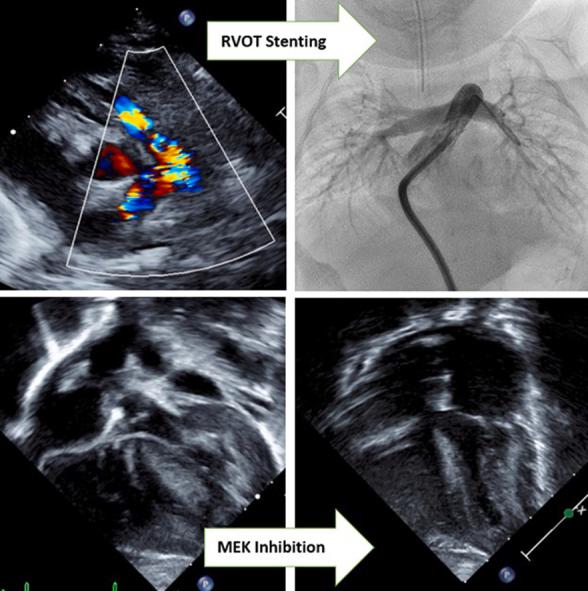

We describe an infant with a history of extreme prematurity, Noonan syndrome, hypertrophic cardiomyopathy, and severe valvular and supravalvular pulmonic stenosis who underwent right ventricular outflow tract stenting and mitogen-activated protein kinase kinase (MEK) inhibitor therapy.

我们描述了一名有极早早产史、努南综合征、肥厚型心肌病以及严重瓣膜和瓣膜上肺动脉狭窄病史的婴儿,该婴儿接受了右心室流出道支架置入术和丝裂原活化蛋白激酶激酶(MEK)抑制剂治疗。

This unique approach ultimately allowed for discharge home and postponement of surgical repair until 18 months of age.

这种独特的方法最终使患儿得以出院回家,并将手术修复推迟至18个月龄。

TAKE-HOME MESSAGES: Right ventricular outflow tract stenting is a viable mode of palliation in infants with Noonan syndrome and pulmonary valve stenosis who are not ideal surgical candidates. An increasing number of case reports are demonstrating the efficacy of MEK inhibition as an effective tool for treatment of Noonan syndrome-associated hypertrophic cardiomyopathy.

对于不适合手术的努南综合征和肺动脉瓣狭窄婴儿,右心室流出道支架置入术是一种可行的姑息治疗方式。越来越多的病例报告表明,MEK抑制作为治疗努南综合征相关肥厚型心肌病的有效工具具有疗效。